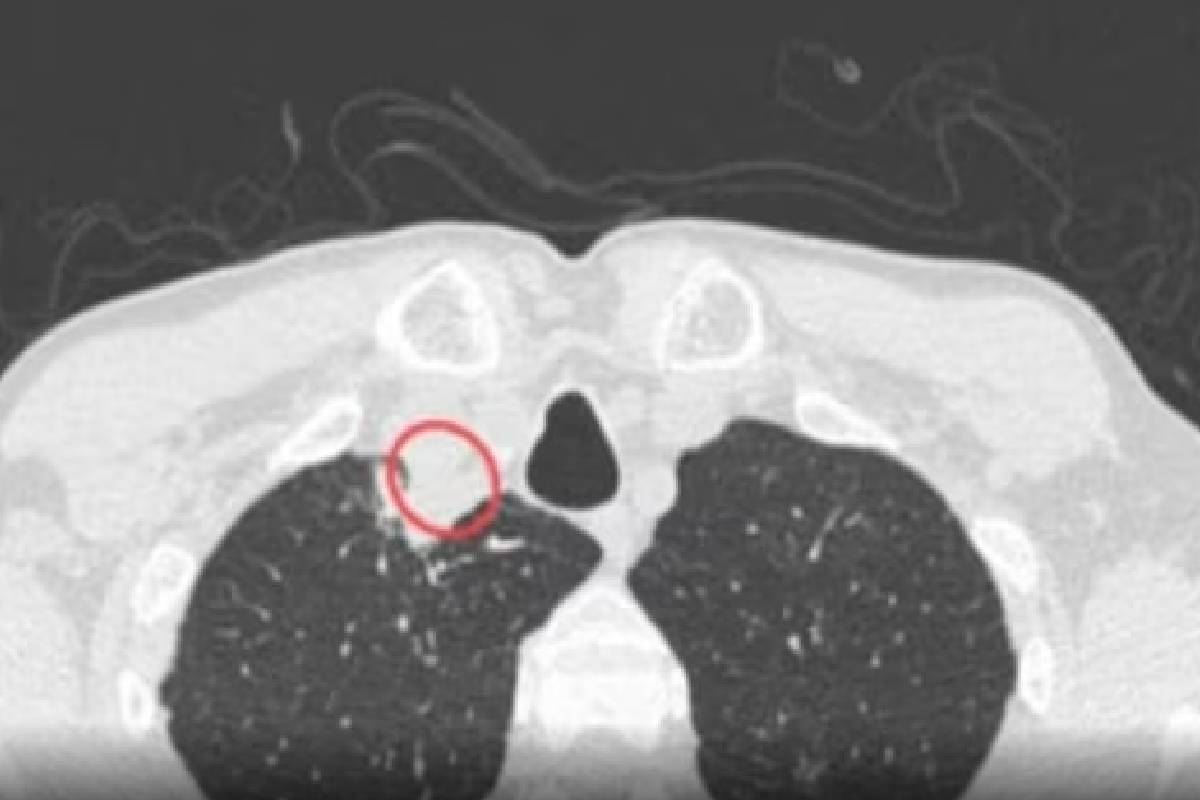

कोलकात, 2 एप्रिल : कोलकाता येथील 61 वर्षांच्या प्लांट मायकोलॉजिस्ट असलेल्या एका व्यक्तीला दुर्मिळ आजार झाला आहे. या आजाराचं नाव प्लांट फंगल डिसीज अर्थात वनस्पती बुरशीजन्य रोग आहे, या आजाराचं निदान झालेली ही जगातील पहिली व्यक्ती आहे. या व्यक्तीला `कॉन्ड्रेस्टेरियम पर्प्युरियम` नावाच्या बुरशीचा संसर्ग झाला आहे. या बुरशीमुळे वनस्पतीला सिल्व्हर लीफ नावाचा आजार होतो. झाडांमधील बुरशीच्या जवळून संपर्कात आल्याने त्याचा संसर्ग मानवामध्ये कसा पसरू शकतो, हे या केसवरून दिसते. असं झालं आजाराचं निदान `एनडी टीव्ही`च्या वृत्तानुसार, मेडिकल मायकोलॉजी केस जर्नलच्या अहवालात म्हटलं आहे की, घोगरा आवाज, थकवा आणि गिळण्यात अडचणी यासारखी लक्षणं तीन महिन्यांपर्यंत कायम राहिल्याने हा रुग्ण डॉक्टरांकडे गेला. अभ्यासानुसार, रुग्णाच्या मानेत पॅराट्रॅचियल गळूदेखील झाले होते. पॅराट्रॅचियल गळूमुळे सामान्यतः ताप येणं, घसा खवखवणं, ओडायनोफॅगिया अर्थात अन्ननलिकेला सूज येणं किंवा वेदना होणे आणि मानेतील हाडांच्या खाली सूज येते. रुग्णाच्या पस म्हणजेच पूचे नमुने तपासले असता त्याला बुरशीजन्य संसर्ग झाल्याचे दिसून आले. त्याच्या छातीच्या एक्स-रेमध्ये कोणताही संसर्ग दिसून आला नाही. परंतु, त्याच्या मानेचा सीटी स्कॅन केला असताना उजव्या बाजूला पॅराट्रॅचियल गळू असल्याचे दिसून आले. अँटिफंगल औषधांचं सेवन `टाईम्स ऑफ इंडिया`च्या वृत्तानुसार, दोन महिने दोन अँटिफंगल औषधं दिल्यानंतर ही व्यक्ती बरी झाली आहे. `या रुग्णाला डायबेटिस, एचआयव्ही संसर्ग, किडनी किंवा इतर कोणताही जुनाट आजार नव्हता. तसेच त्याने इम्युनोसप्रेसिव्ह औषधांचे सेवन केलेले नव्हते. तसेच त्याच्यावर कोणताही आघात झालेला नव्हता. हा रुग्ण व्यवसायाने वनस्पती मायकोलॉजिस्ट आहे. सडणारी सामग्री, मशरुम आणि विविध वनस्पती बुरशी यांच्यावर तो दीर्घकाळ संशोधन करत होता,` असं अभ्यासात म्हटलं आहे. तज्ज्ञ काय म्हणतात? संशोधक तसेच कोलकाता येथील अपोलो मल्टिस्पेशॅलिटी हॉस्पिटलच्या कन्सल्टंट डॉ. उज्ज्वलिनी रे आणि डॉ. सोमा दत्ता यांनी अहवालात म्हटलं आहे की, `रुग्णाला कॉन्ड्रेस्टेरियम पर्प्युरियमचा संसर्ग झाला आहे. हा एक प्लांट फंगस आहे. यामुळे विशेषतः गुलाब कुळातील वनस्पतींना सिल्व्हर लीफ नावाचा रोग होतो. वनस्पतींच्या बुरशीमुळे माणसाला रोग होण्याची ही पहिलीच घटना आहे,’ असं त्यांनी स्पष्ट केलं. `रुग्ण वारंवार कुजणाऱ्या पदार्थांच्या संपर्कात आल्याने त्याला हा दुर्मिळ संसर्ग झाला असावा. या बुरशीजन्य संसर्गाचे निदान मॅक्रोस्कोपिक आणि मायक्रोस्कोपिक मॉर्फोलॉजीवरून स्पष्ट होते. परंतु, संसर्गाचे स्वरूप, प्रसाराची क्षमता आदी गोष्टी निश्चित करणं शक्य झालं नाही,’ असं त्यांनी सांगितलं.